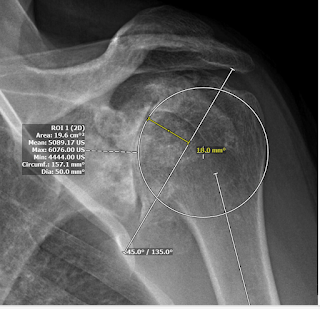

The PACS (Picture Archiving and Communication System) is available to most shoulder surgeon. It has tools for “trying” different prosthetic head sizes as shown below.

50 mm diameter of curvature.

The 54 diameter of curvature intersects the 3 points of the “perfect circle” and reveals the medialization resulting from arthritic humeral head bone loss. However, given the considerable presurgical stiffness that is likely to recur after surgery despite vigorous soft tissue relases, one can anticipate that the 50 mm diameter of curvature might be a better choice if confirmed by intraoperative testing.

Using angle tool at 135º relative to the humeral shaft, the PACS tools can then be used to explore the location of the head cut for this size head component, including its relation to the cuff insertion superiorly and to the osteophytes inferiorly.

Based on this head cut, the thickness of the humeral head implant can be estimated measuring the distance from the medial aspect of the circle to the cut line. This example shows a 20 mm thickness head component.